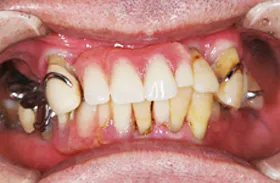

重度の歯槽膿漏のケース

■治療前

■治療後

虫歯と重度の歯周炎(歯槽膿漏)、歯並びに悩まれていたケースです。

■初診時の全体写真

治療のポイント

歯並びを整え、咬合を回復するため、矯正治療を併せてを行いました。

歯が既に抜けていて、骨が吸収してしまっていた部分は、インプラントの埋入に十分な骨量を確保するための骨再生治療(GBR)を行いました。

歯周病によって、歯を支える歯周組織が破壊されてしまっていました。歯を保存するため、再生治療を行いました。

| 主訴 | 数年間、下の奥歯が無いため奥歯で咬めない 歯ならびが悪いため見た目が悪く口を開けて笑えないのとおいしく食事ができない 他院にて歯周病が治らないと言われた |

| 治療方法 | むし歯治療+骨再生療法(GBR)+矯正治療+インプラント治療+補綴治療 |

| 治療期間 | 約3年 |

| 通院回数等 | 約40回 |

| 費用 | 約500万円 |

| リスク・副作用 | 術後の腫れ・痛み |